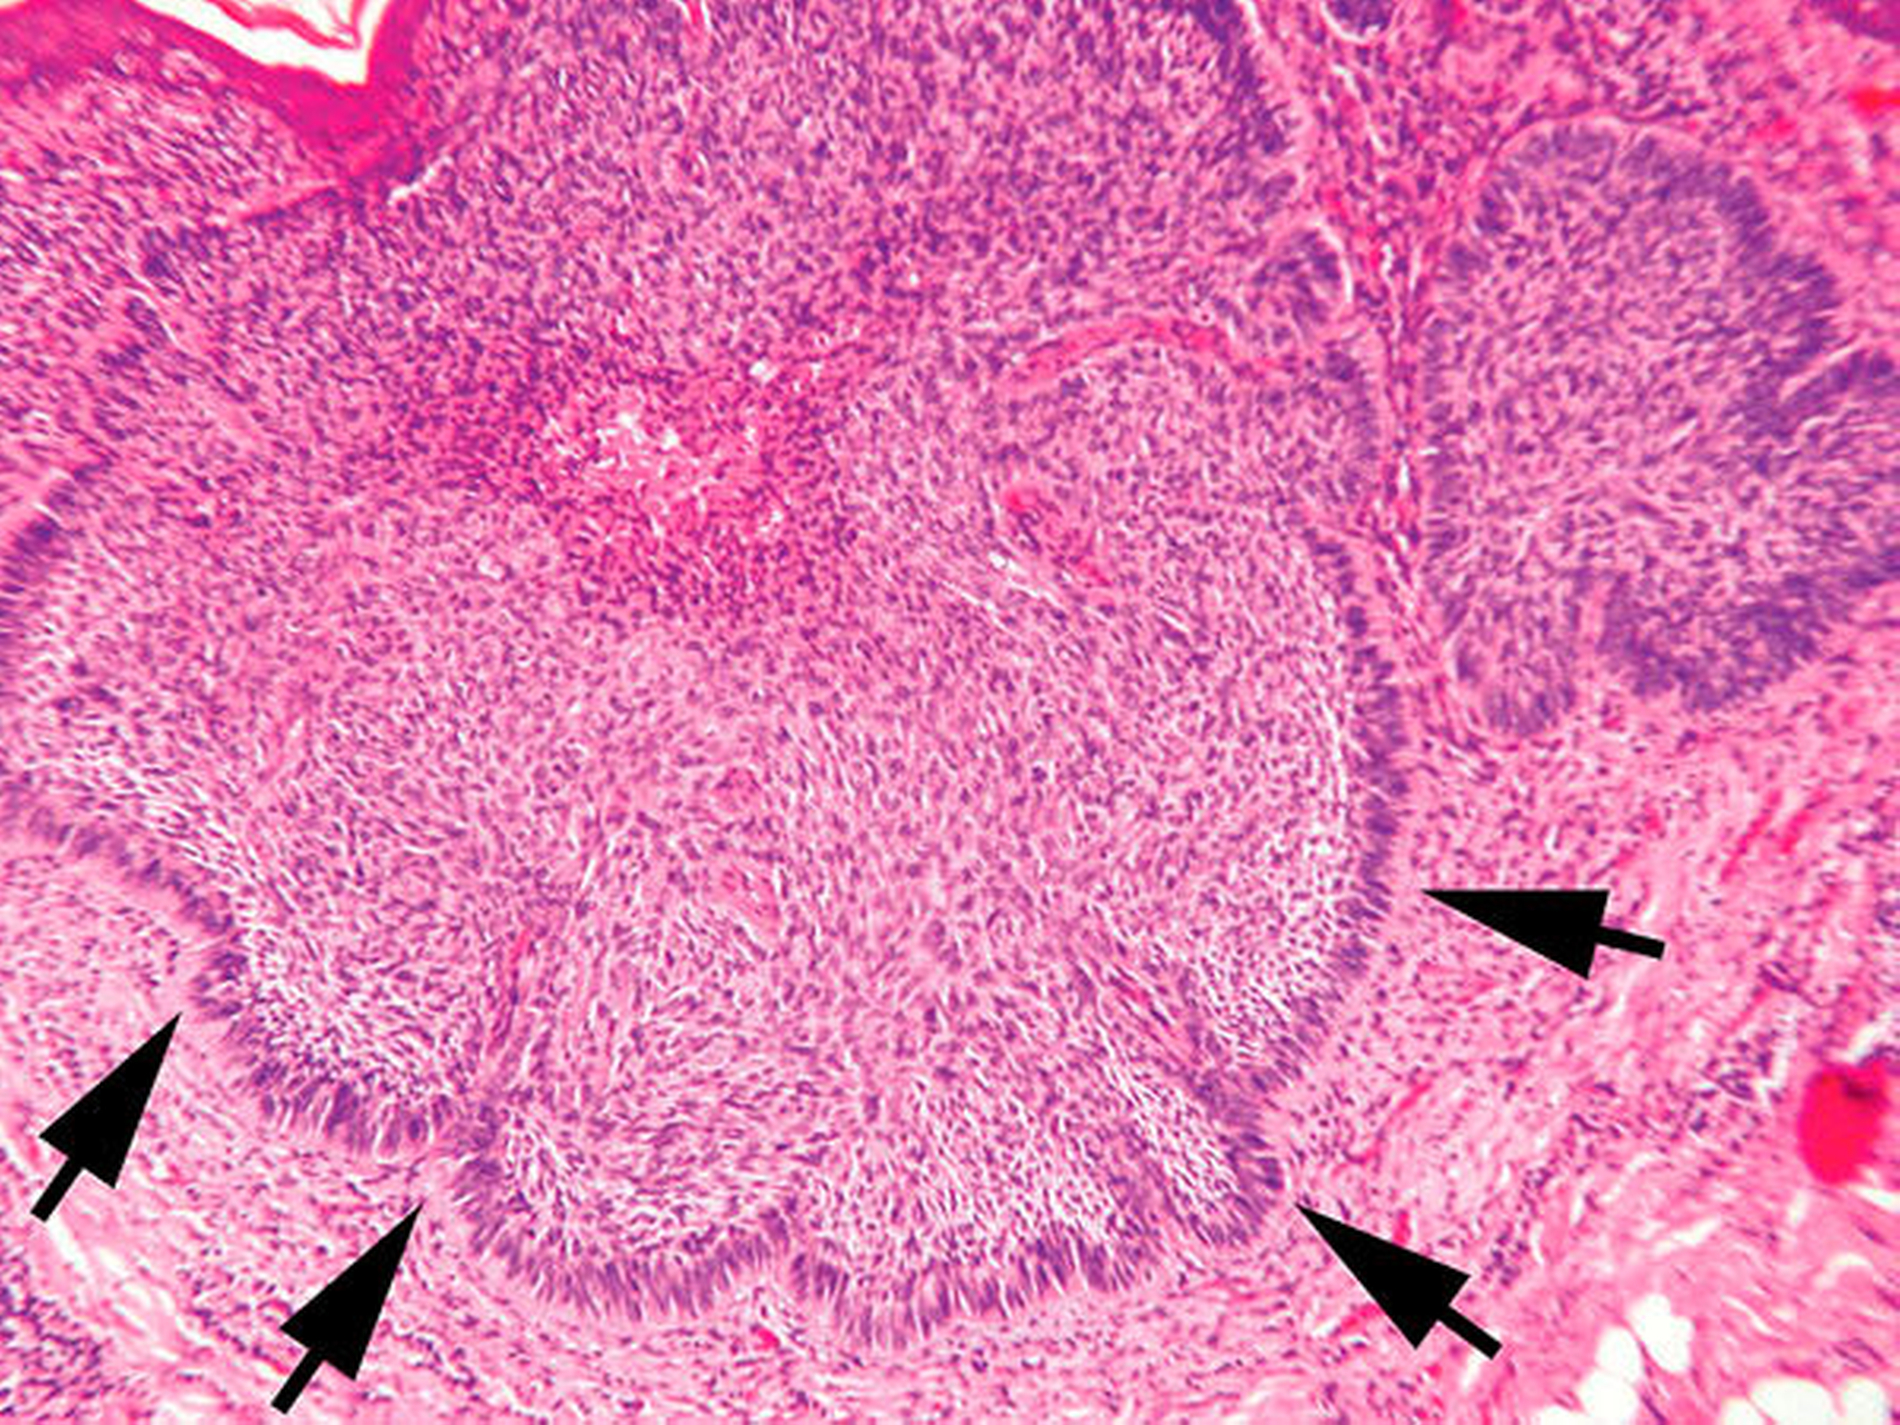

Die histopathologische Aufbereitung des Gewebes (Abbildungen 3 bis 6) bestätigte dabei die Diagnose eines Basalzellkarzinoms.

Die Diagnose wird vornehmlich klinisch gestellt und dann histopathologisch verifiziert. Es gibt unterschiedliche Subtypen, wie zum Beispiel das noduläre, das superfizielle, das sklerodermiforme Basalzellkarzinom und dann den Ulcus rodens und den Ulcus terebrans. Am häufigsten ist das noduläre Basalzellkarzinom als scharf abgegrenzter und flach erhabener Tumor, der gelblich-rötlich imponiert und häufig einen perlschnurartigen Randsaum aufweist, mit den typischen Teleangiektasien, die von peripher nach zentral ziehen. Das sklerodermiforme Basalzellkarzinom unterscheidet sich hiervon vornehmlich durch die weitaus schlechtere Abgrenzbarkeit. Bei Bestehen der Karzinome über einen längeren Zeitraum können diese ulzerieren (Ulcus rodens) und in der Folge auch tiefer liegende Strukuren zerstören (Ulcus terebrans) [Hauschild A et al., 2012].